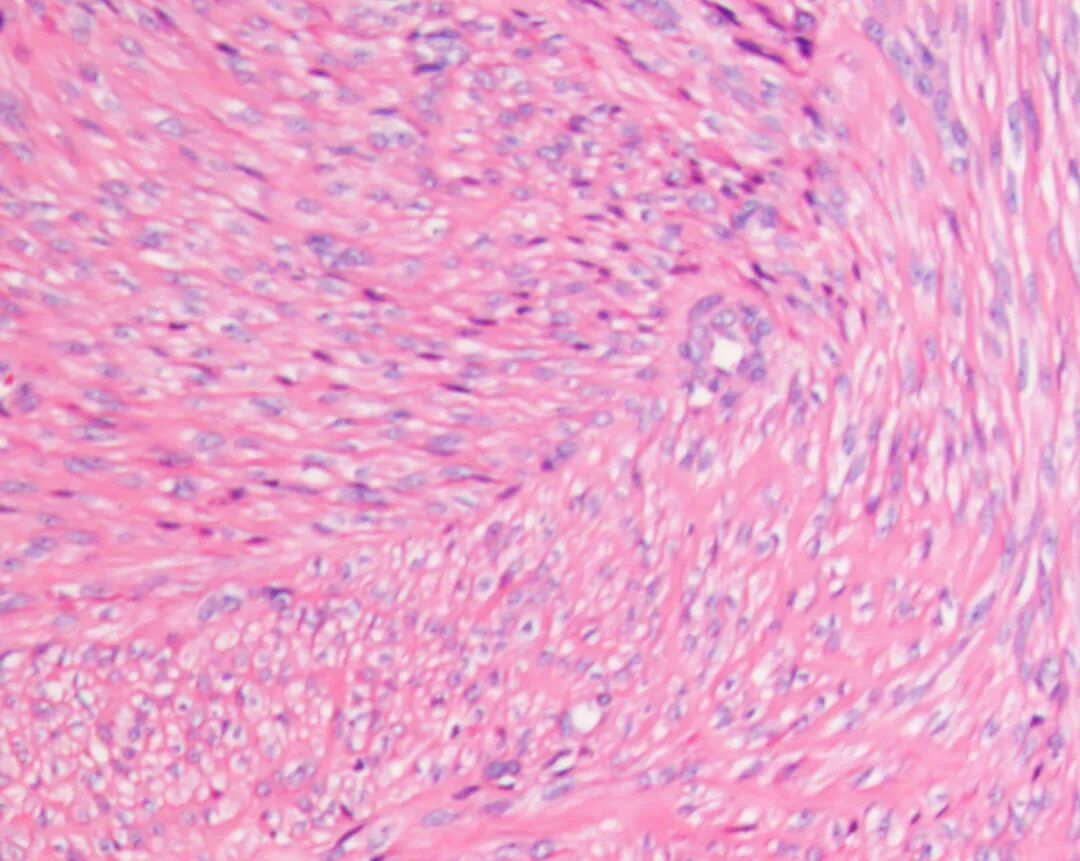

富于细胞型平滑肌瘤

显微镜下可以看到:

平滑肌细胞排列更加紧密

细胞数量明显增多

纤维组织相对减少

因此被称为“富于细胞型”。

富于细胞型肌瘤通常表现为:

细胞多但排列规则

几乎没有异型细胞

核分裂极少

没有坏死